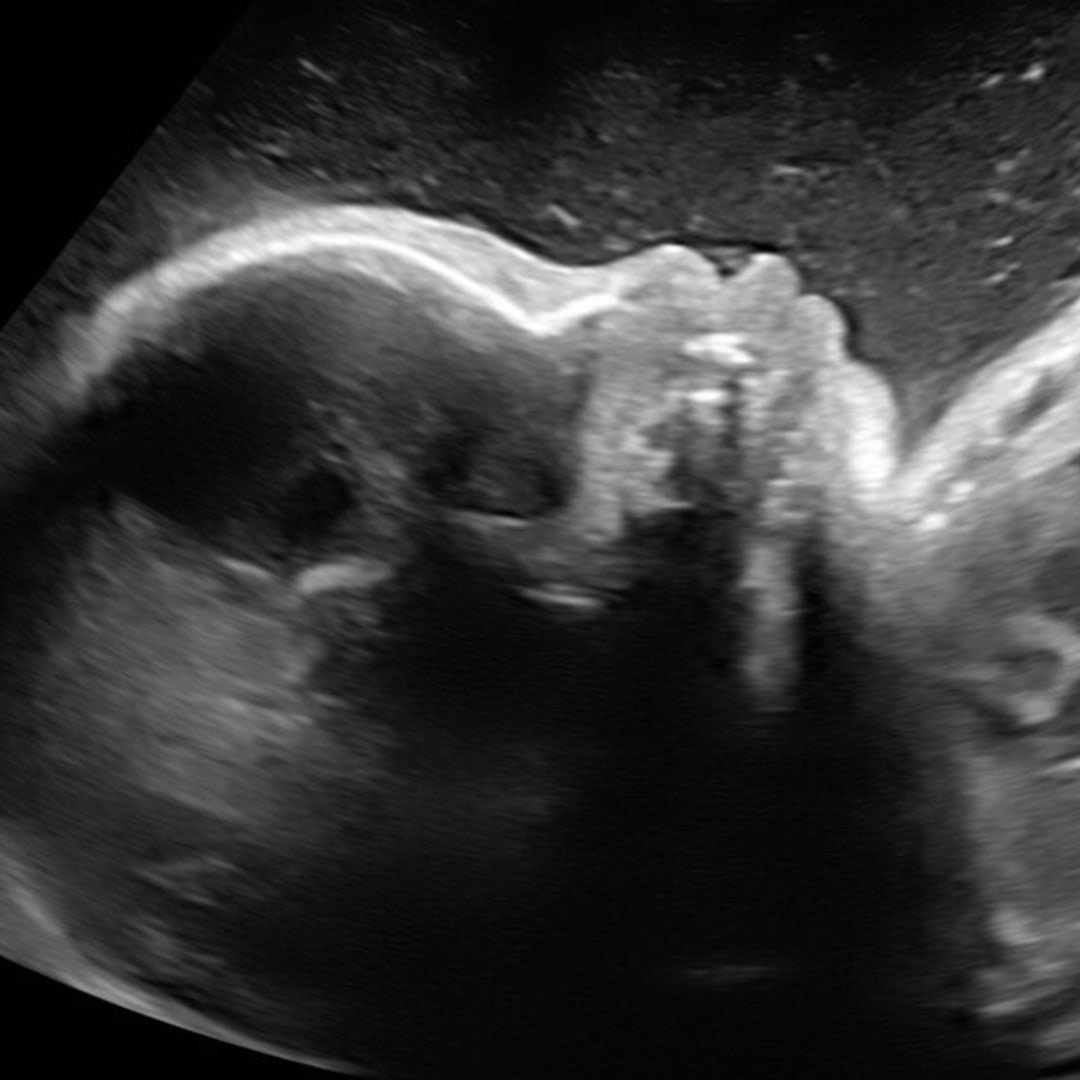

Baby girl!